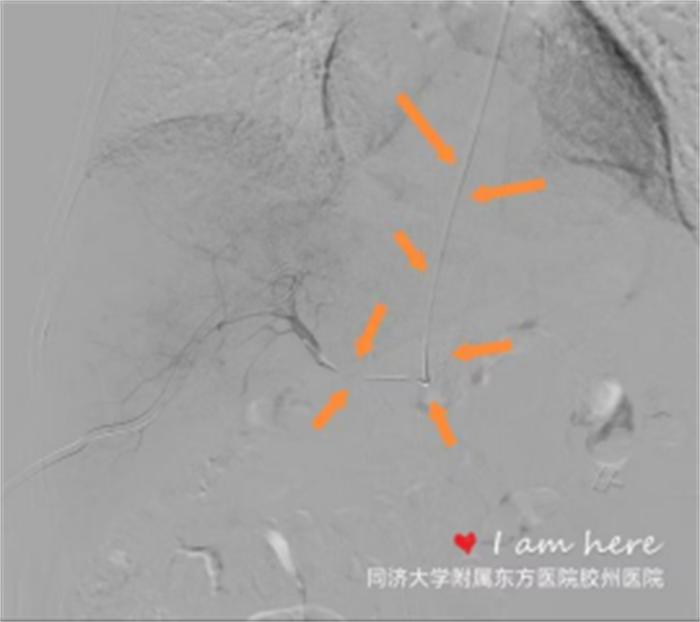

手术当天,在团队的密切配合下,刘敬禹精准选取患者右侧肘部肱动脉远端作为穿刺点,以微穿刺针小心翼翼穿刺后,置入微导丝;随后沿微导丝缓慢送入微导管,在导丝导管紧密配合下,充分利用DSA 路途技术及工作位角度等技术,确保导管精准定位。最终,成功将微导管送入肝动脉内,并顺利造影。整个过程患者无明显不适,手术顺利完成。